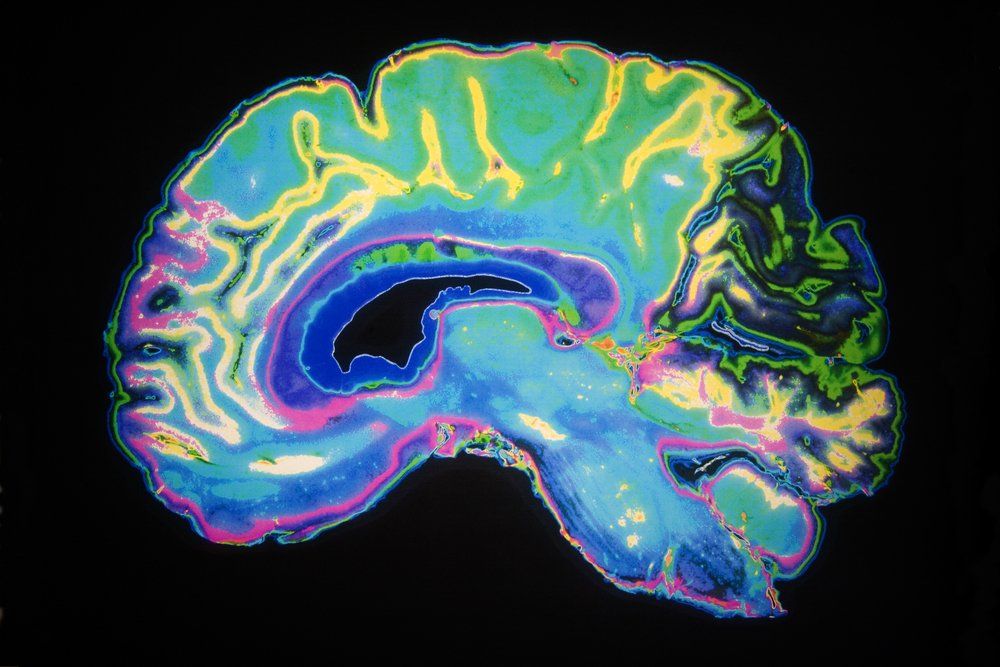

Identification of a brain circuit implicated in Alzheimer disease and schizophrenia could aid in comprehension of brain disorders and point to prevention strategies.

These findings advance knowledge about the link between brain inflammation and the progression of brain disorders and suggest possible targets for future treatments.